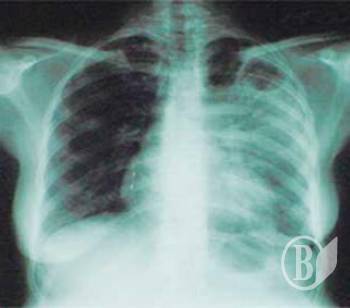

Самой распространённой формой был активный туберкулёз лёгких. С диагнозом этой болезни в прошлом году зарегистрировано 833 больных против 755 в 2007г.